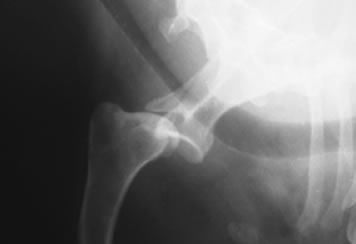

肩関節脱臼

症状:飛び降りた拍子、高所から落下した拍子、もしくは普通の生活の中で起こった突然の前足の挙上

肩関節脱臼とは

肩関節が外れた状態、内方脱臼と外方脱臼があります。

レントゲン検査

手術をせずに整復し固定をおこなっても治ることが少なく、外科的に脱臼を整復し固定する必要がある場合が多いです。内方脱臼ではスーチャーアンカーを用いて整復する方法など、外方脱臼では二頭筋腱の転移術などを行います。それでも再脱臼する場合、最終的な救済処置として関節固定術を行うこともあります。